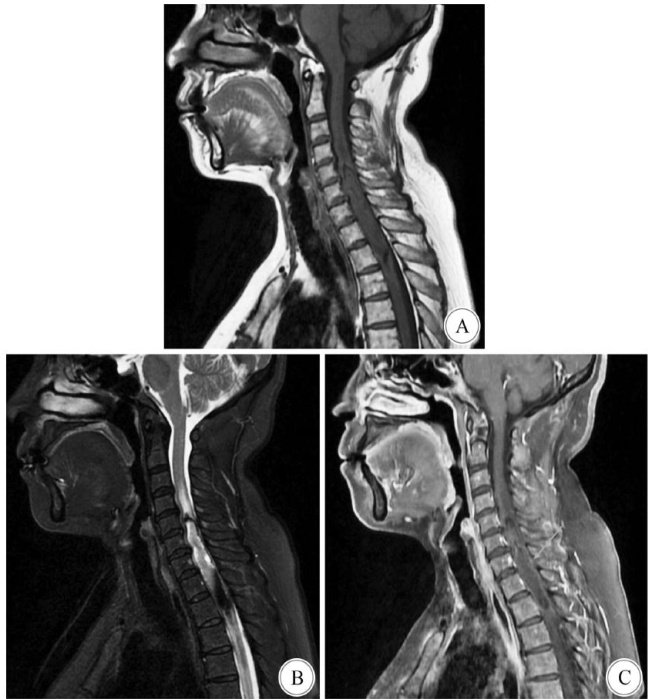

Abstract:ObjectiveTo investigate the clinical manifestations,diagnosisand treatment of intramedullary glioependymal cyst(GEC).MethodsThe clinical data of a patient with C5-T2 segment intramedullary GEC admitted tothe Nerve Tumor Diagnosis and Treatment Center of Shiyan Hospitalin December 2O24 were retrospectively analyzed,and the related literatures were reviewed.ResultsThe patient was admited to the hospital due to pain and numbness in both upper limbs.MRI showed an intramedullary C5-T2 space-occupying lesions in the spinal cord,which was confirmed by postoperative pathology as C5-T2 intramedullary GEC. MRI reexamination on the 3rd day after surgery showed total tumor resection,no recurrence was found at 3 months, andthepatient returned to daily life with normal limb movement at 6-month follw-up.Conclusions Intramedullry GEC inthe cervicothoracic segment isextremely rare.MRI combinedwith pathological immunohistochemistry can confirm the diagnosis.Microsurgical total resection isaneffective treatment with favorable prognosis.